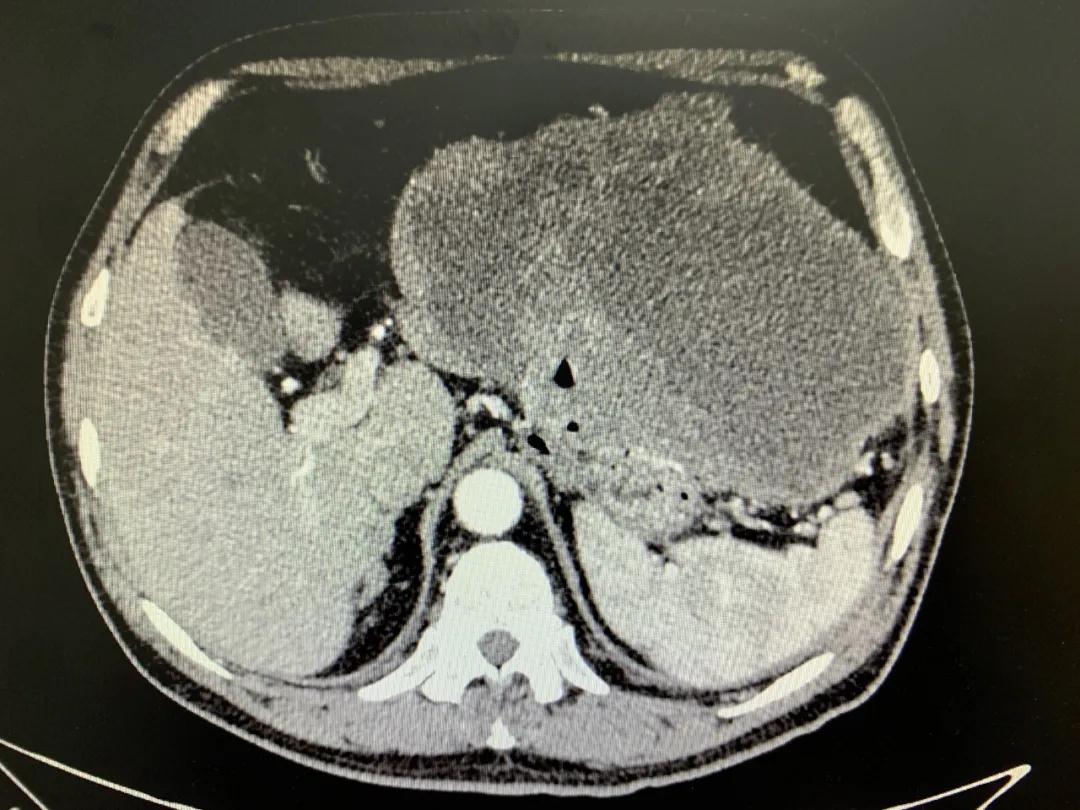

患者入院時血紅蛋白數(shù)值仍持續(xù)下降,出現(xiàn)失血性休克表現(xiàn),危及生命。消化外科二病區(qū)蔡磊主任接診后,組織科室迅速對患者進行了全面的檢查。CT提示腫瘤大小約19.3*10.3cm,腫瘤內(nèi)提示大量積血。結(jié)合相關(guān)檢查,考慮為罕見的巨大胃間質(zhì)瘤合并出血。